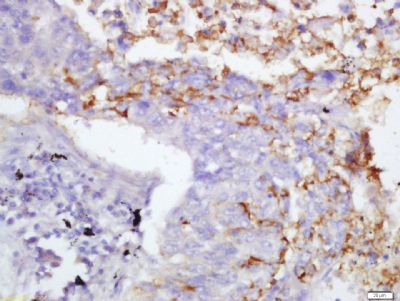

Fibrinogen beta chain,纤维蛋白原β链抗体产品应用WB=1:100-500 ELISA=1:500-1000 IHC-P=1:100-500 IHC-F=1:100-500 ICC=1:100-500 IF=1:100-500 (石蜡切片需做抗原修复)